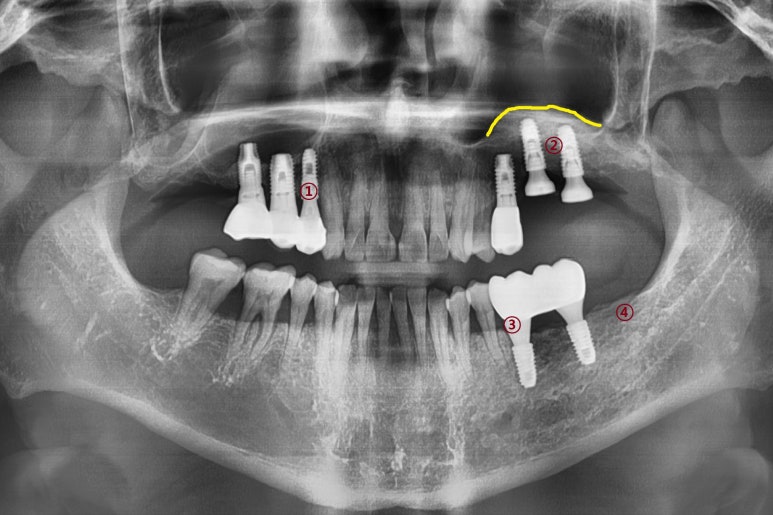

간단한 상악동 수술이 아니라 복잡한 고난이도의 상악동 수술이 필요했는데

상악동을 들어올려 뼈이식을 하고(노란색으로 표시된 부분)

임플란트 2개를 심은 모습입니다. [②로 표시된 부분]

나머지 ①③ 표시된 부분도 원장님께 임플란트 수술을 받으셨습니다.

④로 표시된 부분은 사랑니 발치한 부분입니다.

원장님께 수술 받은 3군데 임플란트 5개 모두 잘 쓰고 계십니다.